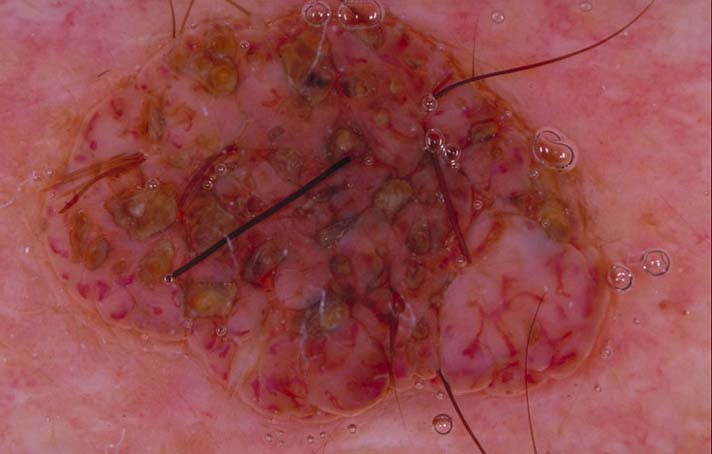

| 119 "diagnosis.char"="Basal Cell Carcinoma" "comment.char"="" "features.char"="Absent pigment network AND one or more of:|Arborising vessels" | "diagnosis.char"="" "breslow_depth.float"="0" "comment.char"="" "features.char"="" |  |  |